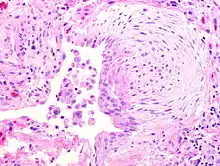

![]() | Fibroadenoma | A well circumscribed lesion showing proliferation of intralobular stroma compressing and distorting the epithelium. | Category: Histopathology of breat fibroadenomas | Fibroadenoma |

![]() | Fibroadenoma | A well circumscribed lesion showing proliferation of intralobular stroma compressing and distorting the epithelium. | Category: Histopathology of breast fibroadenomas | fibroadenoma |